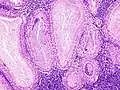

The appearance of this tumor under the microscope is unique. There are cystic spaces surrounded by two uniform rows of oncocytes, which are epithelial cells with abundant, granular, eosinophilic cytoplasm.[7] The cystic spaces have epithelium referred to as papillary infoldings that protrude into them. Additionally, the epithelium has lymphoid stroma with germinal center formation.

Histopathology of Warthin tumor in the parotid gland. H&E stain.

Histopathology of Warthin tumor in the parotid gland. Another view of a file "Warthin tumor (1).jpg". H&E stain.

Histopathology of Warthin tumor in the parotid gland. Higher magnification of a file "Warthin tumor (1).jpg". H&E stain.